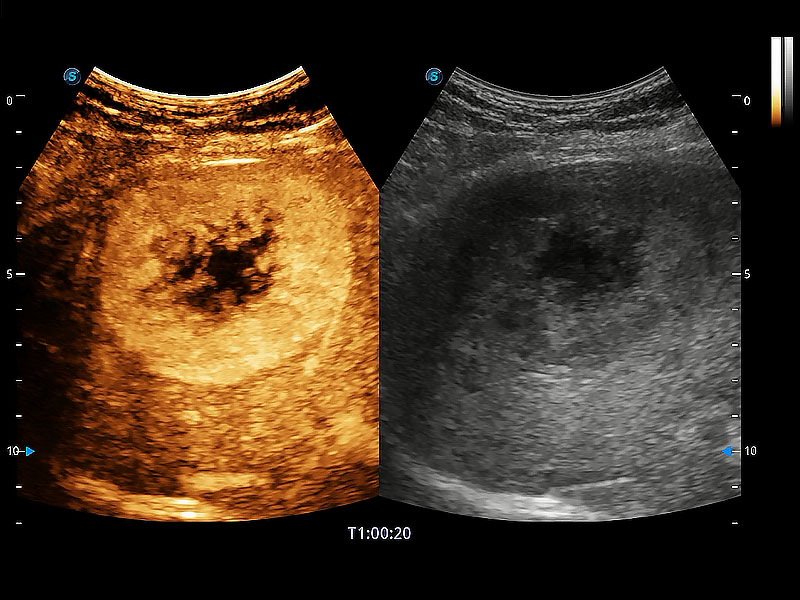

• 全面的造影成像

非线性融合造影成像充分利用谐波和基波信号,为难以观察的血流进行增强显像。可用于线阵、凸阵、微凸阵、相控阵探头。

优异的基础图像

ProPet 80 全新的动物超声智能软件和丰富的探头群,为动物医生提供了高清晰度和精细分辨率的图像,无论在宠物、马科、畜牧还是实验室动物等应用中都可以轻松应对,为您的日常工作带来满意的体验。

(犬)肝脏

(猫)胆囊

(犬)肾脏显微血流